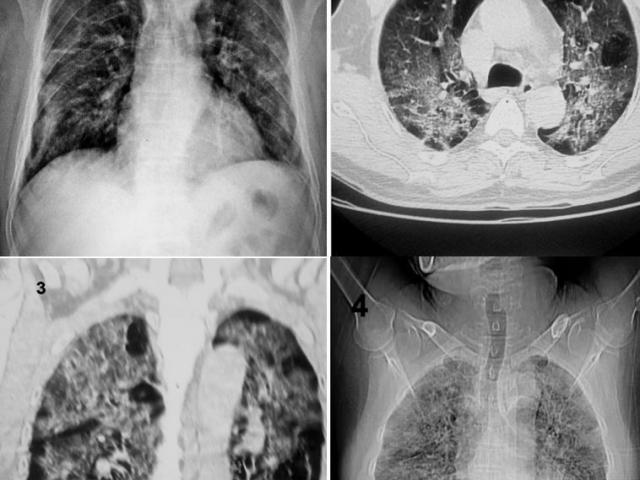

Ảnh minh họa